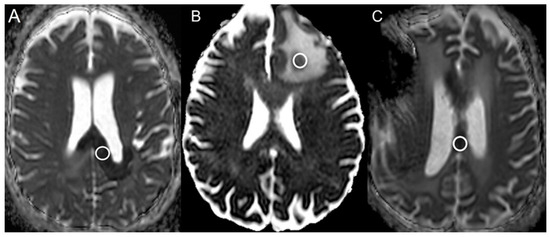

| Bevacizumab | 21 | 248.1 ± 67.2 | 647.2 ± 94.6 | <0.001 |

| Bevacizumab | 21 | 0.39 ± 0.10 |